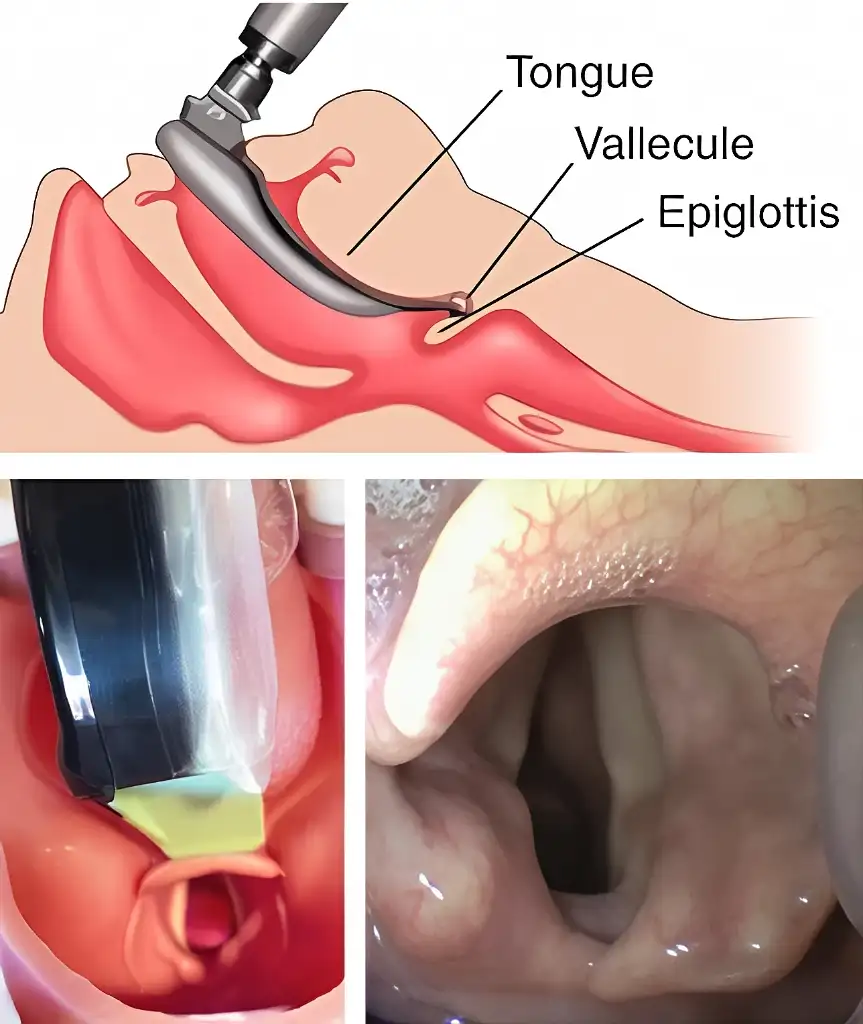

MacIntosh vs Miller

MacIntosh Blade in the Vallecula (preferred)

Airtraq allows both techniques

Macintosh style is the preferred option since it requires less upward traction and therefore it is softer on patient tissues.

If the Airtraq is already underneath the epiglottis and the user prefers to intubate Macintosh style withdraw the Airtraq until the epiglottis falls and advance the tip of the blade into the vallecula.

Miller Blade underneath Epiglottis